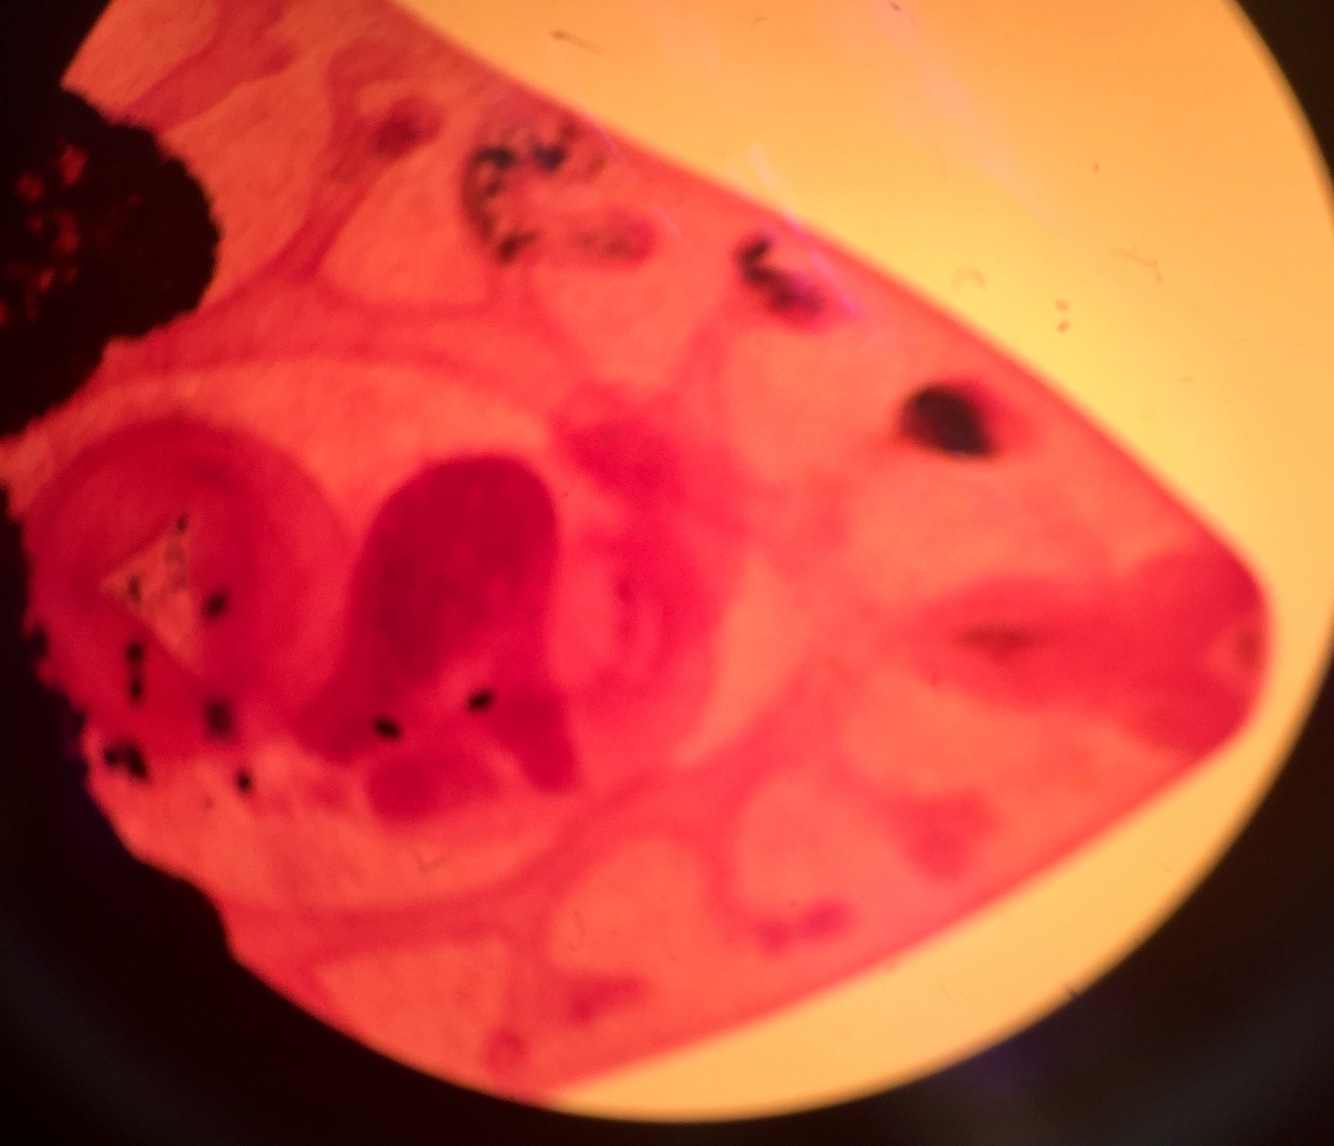

Genus species?

Structures?

Taenia solium “Pork tapeworm”

Proglottids, eggs in the Gravid proglottids

Kingdom?

Phylum?

Species genus?

Infected by?

Difinitive host?

Intermediate host?

Symptoms?

Locate structures

Animalae

Platyhelminthes

Infected? Undercooked pork eaten

Difinitive host? Pig

Intermediate host- Human

Symptoms? Not severe

Image- Scolex, Hooks